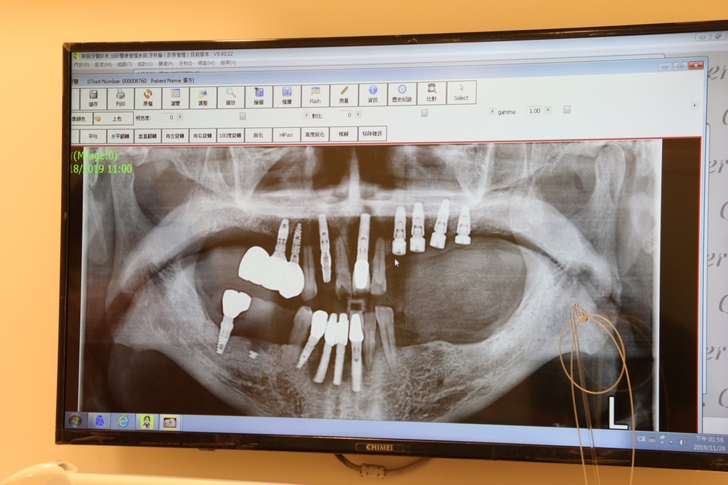

別看醫師一頭白髮蒼蒼評估植牙前醫師檢查口腔健康衛生可是非常嚴謹,劉醫師仔細審視X光片再環顧口腔牙齒情況,先替口內牙齒通通清洗一遍之後,才建議那缺很久的臼齒可以做植牙或是牙橋來補缺牙,雖旁邊臼齒有些傾倒,若沒有矯正預算可以不用刻意將倒牙扶正也能做植牙手術,未來只要多加注意清潔就好,然後櫃台護士就會協助說明微創植牙費用及植牙手術療程時間。